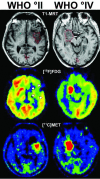

Imaging in patients with brain tumors aims toward the determination of the localization, extend, type, and malignancy of the tumor. Imaging is being used for primary diagnosis, planning of treatment including placement of stereotaxic biopsy, resection, radiation, guided application of experimental therapeutics, and delineation of tumor from functionally important neuronal tissue. After treatment, imaging is being used to quantify the treatment response and the extent of residual tumor. At follow-up, imaging helps to determine tumor progression and to differentiate recurrent tumor growth from treatment-induced tissue changes, such as radiation necrosis. A variety of complementary imaging methods are currently being used to obtain all the information necessary to achieve the above mentioned goals. Computed tomography and magnetic resonance imaging (MRI) reveal mostly anatomical information on the tumor, whereas magnetic resonance spectroscopy and positron emission tomography (PET) give important information on the metabolic state and molecular events within the tumor. Functional MRI and functional PET, in combination with electrophysiological methods like transcranial magnetic stimulation, are being used to delineate functionally important neuronal tissue, which has to be preserved from treatment-induced damage, as well as to gather information on tumor-induced brain plasticity. In addition, optical imaging devices have been implemented in the past few years for the development of new therapeutics, especially in experimental glioma models. In summary, imaging in patients with brain tumors plays a central role in the management of the disease and in the development of improved imaging-guided therapies.